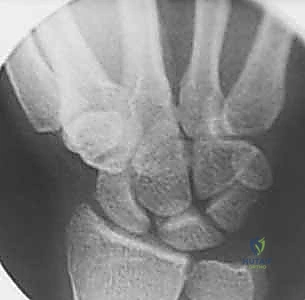

* Static Instability Signs (Lateral view):

* Increased Scapholunate Angle: Measured by drawing lines through the longitudinal axes of the scaphoid and lunate. Normally 30-60 degrees. An angle greater than 60 degrees indicates scaphoid flexion.

* DISI Deformity: A radiolunate angle greater than 15 degrees indicates the lunate is extended dorsally.

FIG 2 • (continued) D. A lateral radiograph demonstrating an increased scapholunate angle.